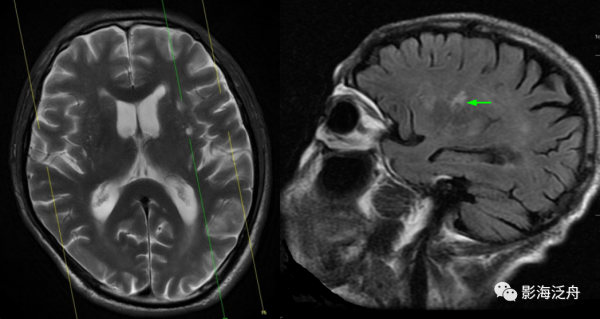

病例二:21歲女性患者,頭痛數月前來就診。左側基底節區多發囊性病灶,部分突入第三腦室室間孔區域並引起梗阻性腦積水(紅箭),病灶簇狀分佈,呈規則的圓形或類圓形,灶周無明顯水腫,增強未見任何強化,符合擴大V-R腔隙的典型特徵。值得注意的是,擴大的VR腔隙一般不會引起佔位性效應。